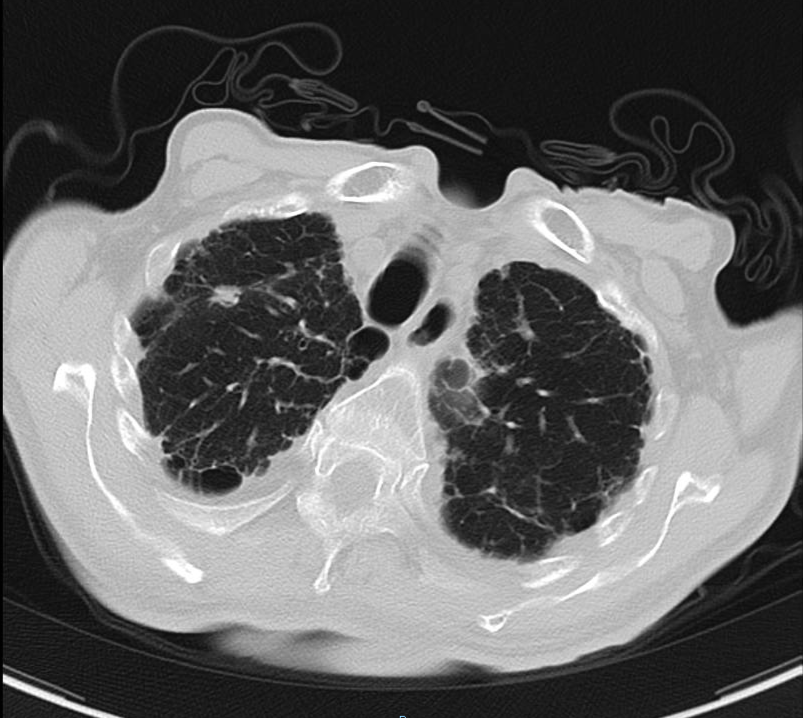

2020-01-08查胸部CT:双肺间质纤维化伴双肺气肿,双肺炎症,伴支气管扩张,右肺上叶结节样影,性质待定,双侧胸腔积液,纵膈多发肿大淋巴结,主动脉及冠状动脉硬化。

2020-08-31复查胸部CT:右肺结节影,结合病史考虑转移性病变,左侧局限性气胸,双肺气肿,双肺间质性病变,双侧胸腔积液;心脏增大,主动脉硬化。